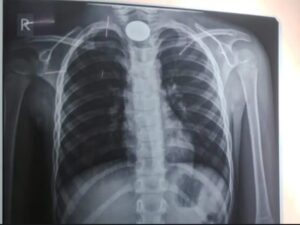

प्राथमिक जांच और एक्स-रे के बाद रात 8 बजे बच्चे को ऑपरेशन थिएटर में शिफ्ट किया गया। चिकित्सकों ने बिना चीरा लगाए एंडोस्कोपी तकनीक का उपयोग करने का निर्णय लिया। इस प्रक्रिया में कैमरे की सहायता से सिक्के की सटीक स्थिति देखी गई और विशेष उपकरणों की मदद से उसे सावधानीपूर्वक बाहर निकाला गया।

डॉ. साहू के अनुसार जैसे ही एंडोस्कोप डाला गया, मॉनिटर पर सिक्का स्पष्ट दिखाई दिया। पूरी प्रक्रिया के दौरान एनेस्थीसिया टीम बच्चे के ऑक्सीजन स्तर पर लगातार नजर बनाए हुए थी। करीब 20 मिनट की सावधानीपूर्ण प्रक्रिया के बाद सिक्का सफलतापूर्वक निकाल लिया गया, जिसके बाद बच्चे ने राहत की सांस ली।